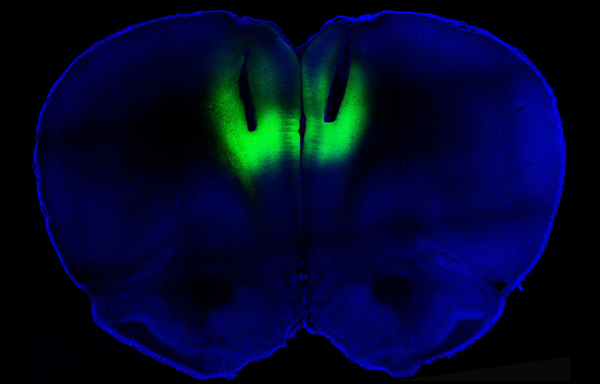

To find out whether those sluggish neurons in turn caused the compulsive behavior, the scientists turned to a technique called optogenetics, which uses light to turn neurons on or off. The researchers injected the rats with viruses that inserted light-responsive molecules into the lazy neurons. When the researchers used lasers to stimulate the neurons in the compulsive rats, the rats pushed the levers one-third as often. The same experiment on rats that hadn’t been shocked had no effect.